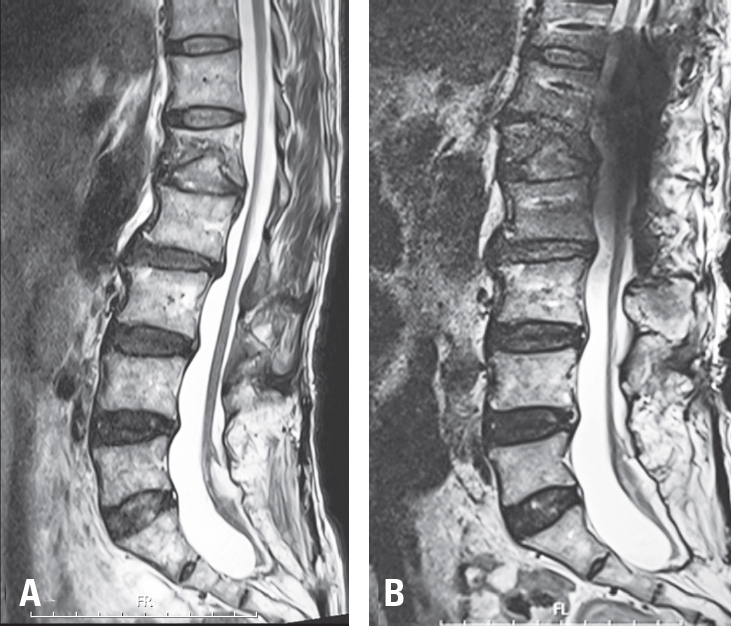

Fig. 4.

Pre-and post-operative sagittal T2WI MR image. (A) The marked kyphosis between T12 and L2 results in visible stretching of the spinal cord. (B) After reduction of the T12–L2 kyphosis and lowering of the spinal column height, the spinal cord appears slightly loosened and less tensioned.

The patient tolerated the procedure well without any intraoperative adverse events or signal changes in IONM. Immediate postoperative plain radiographs demonstrated a reduction in local kyphosis by approximately 28 degrees and a decrease in the spinal column height of approximately 10 mm at the osteotomy site (Fig. 2). MRI obtained on postoperative day 2 revealed distinct interval relaxation of the spinal cord compared with preoperative images, indicating an effective release of longitudinal tension (Fig. 4).